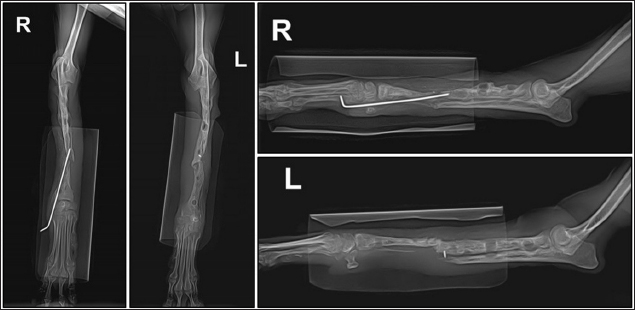

A two-step surgical plan was developed for managing the fractures. The remaining pin was removed in the first surgery and a CEF was applied for temporary fixation (Fig. 2A and B). Pins used included two 0.9 mm K-wires placed proximally and distally in a crossed manner, and one 1.2 mm olive wire placed in a single location. Anticipation of bone regeneration around areas of bone lysis near screw holes, and physical rehabilitation focused on inducing forelimb use until the second surgery. During the 6-week maintenance period of the temporary external fixation device, partial bone regeneration was observed in some areas of bone loss (Fig. 2C and D). Although forelimb ambulation remained plantigrade, there was an improvement in utilizing the limb smoothly with weight-bearing. In the second surgery, the CEF device was removed, and a surgical approach was made to apply the bone plate. The atrophied fracture sites on both sides showed no signs of bone regeneration and were partially debrided to expose the bone marrow cavities. The fracture was then fixed with a long bone plate and 1.5 mm screws. Autografts were harvested from the iliac wing and transplanted around the fracture site. This procedure was performed identically on both limbs with the fascia and skin closed in a standard manner. Additionally, CEF methods involved applying 0.9 mm K-wires, the same size as those used in the first surgery, above and below the plate on the fractured radius to provide further stability (Fig. 3).

Preoperative medications for both surgeries included tramadol (5 mg/kg, IV), cefazolin (30 mg/kg, IV), famotidine (0.5 mg/kg, IV), and midazolam (0.2 mg/kg, IV). General anesthesia was induced with propofol (5 mg/kg, IV) and maintained with 1.5%–2% isoflurane in oxygen. Intraoperative analgesia was provided by a constant-rate infusion of ketamine and lidocaine. The forelimbs were then prepared for routine aseptic surgery. The entire surgery lasted 2 hours and 50 minutes. Postoperatively, cefazolin was administered for 5 days, along with tramadol and meloxicam (0.1 mg/kg, SC) for pain management. Amoxicillin syrup was prescribed for an additional 3 weeks as an antibiotic. Sutures were removed in the second postoperative week, and ongoing physical rehabilitation was implemented. External fixation devices were removed in the fourth postoperative week. Radiographic assessments showed a union of the right radius by the eighth postoperative week and the left radius by the tenth postoperative week (Fig. 4). Although forelimb ambulation remained plantigrade, the dog’s overall gait improved, enabling consistent quadrupedal movement.

Fig. 3. Lateral radiograph of bilateral radius and ulna fracture reduced using circular external fixation along with plate and screw fixation.